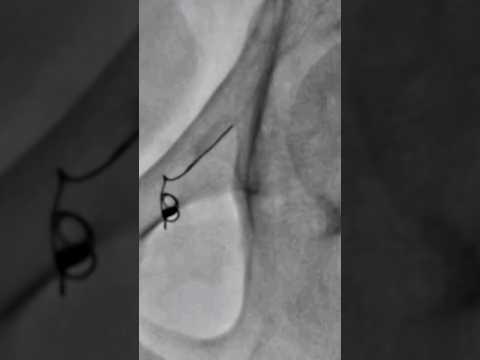

Varicocele embolization live case - Step 7 #nosurgery | Dr. Gaurav Gangwani